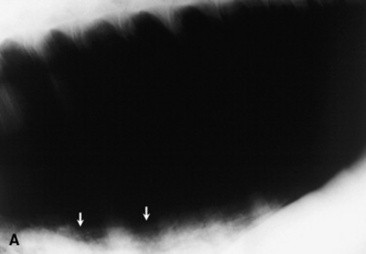

Histoplasmosis is caused by the saprophytic, dimorphic fungus H. capsulatum, which is most prevalent in moist soil containing bird or bat waste. Yeast organisms are 2 to 4 μm in diameter, with a thin clear halo surrounding a round or crescent-shaped basophilic cytoplasm (Fig. 31-24). Histoplasmosis has been reported in less than 10 equine cases,330 and thus horses are considered to be relatively resistant to disease. H. capsulatum may occur in an enteric, pulmonary, or disseminated form.330H. capsulatum was identified in pulmonary granulomas in a horse dying of chronic Yersinia colitis372 and in another horse with intestinal salmonellosis.373 It has also been associated with abortions and severe granulomatous pneumonia in neonatal foals (Fig. 31-25) and a yearling.374 Successful treatment with amphotericin B was reported in a filly with pulmonary histoplasmosis diagnosed by cytologic identification of the organism on a tracheal wash smear and from a lung aspirate.330

image

Fig. 31-25 Lateral thoracic radiographs from a foal with Histoplasma pneumonia.

Courtesy Carol Clark, Peterson and Smith Equine Hospital, Ocala, Fla.

Treatment with amphotericin B or itraconazole is recommended (see Table 31-7).